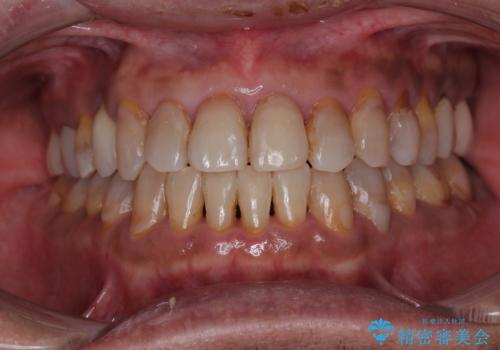

前歯のでこぼこをスッキリと 目立たない装置による抜歯矯正

でこぼこの解消とともに、やや閉じにくそうな口元を引っ込めることを目的とし、上下左右の第一小臼歯4歯を抜歯をしてワイヤー矯正により治療することとしました。

周りの方からも整った歯列を羨ましいとおっしゃっていただけるようになり、患者様には大変満足していただきました。